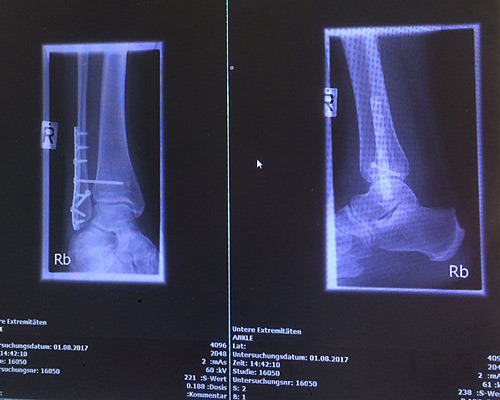

… habe ich jetzt eine Schraube locker. Gebrochen ist die Stellschraube nicht, aber auch nicht mehr “auf Spannung”. Geht aber. Ansonsten befand der Arzt heute, das die in Sanderbusch gute Arbeit gemacht haben und Lena hatte einen Heidenspaß, weil wir doch mit dem Rolli los waren und ich dann die ganze Zeit rückwärts gefahren bin und mich mit dem gesunden Fuß abgestoßen habe. Morgen fährt mich eine Freundin zur Physio, Jana radelt wieder selber zur Schule und Lena wird von der Mutter des Geburtstagskindes zur Feier mitgenommen.

MRT vom Fuß sollte ich momentan wohl lieber nicht machen lassen und jede Sicherung am Flughafen hätte auch ihren Spaß mit mir *g*.